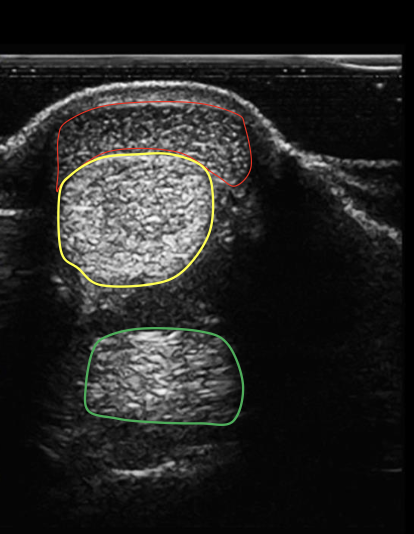

what structure is circled in red?

superficial digital flexor tendon

what structure is circled in yellow?

deep digital flexor tendon

what structure is circled in green?

suspensory ligament